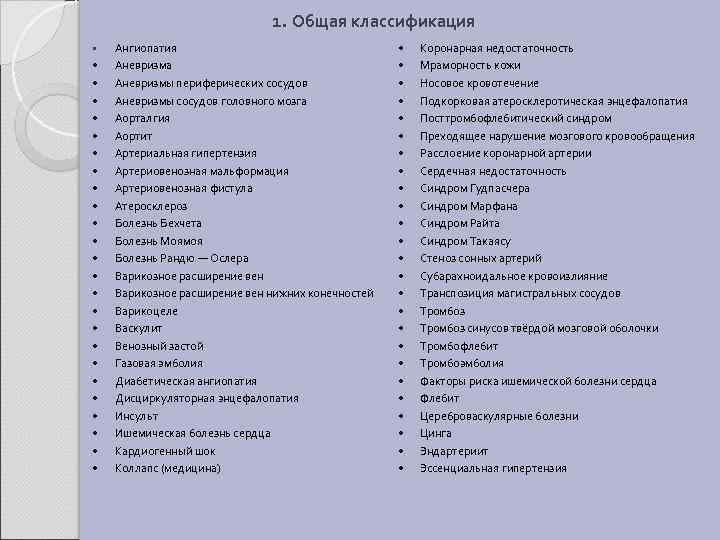

1. Общая классификация • • • • • • • Ангиопатия Аневризма Аневризмы периферических сосудов Аневризмы сосудов головного мозга Аорталгия Аортит Артериальная гипертензия Артериовенозная мальформация Артериовенозная фистула Атеросклероз Болезнь Бехчета Болезнь Моямоя Болезнь Рандю — Ослера Варикозное расширение вен нижних конечностей Варикоцеле Васкулит Венозный застой Газовая эмболия Диабетическая ангиопатия Дисциркуляторная энцефалопатия Инсульт Ишемическая болезнь сердца Кардиогенный шок Коллапс (медицина) • • • • • • • Коронарная недостаточность Мраморность кожи Носовое кровотечение Подкорковая атеросклеротическая энцефалопатия Посттромбофлебитический синдром Преходящее нарушение мозгового кровообращения Расслоение коронарной артерии Сердечная недостаточность Синдром Гудпасчера Синдром Марфана Синдром Райта Синдром Такаясу Стеноз сонных артерий Субарахноидальное кровоизлияние Транспозиция магистральных сосудов Тромбоз синусов твёрдой мозговой оболочки Тромбофлебит Тромбоэмболия Факторы риска ишемической болезни сердца Флебит Цереброваскулярные болезни Цинга Эндартериит Эссенциальная гипертензия